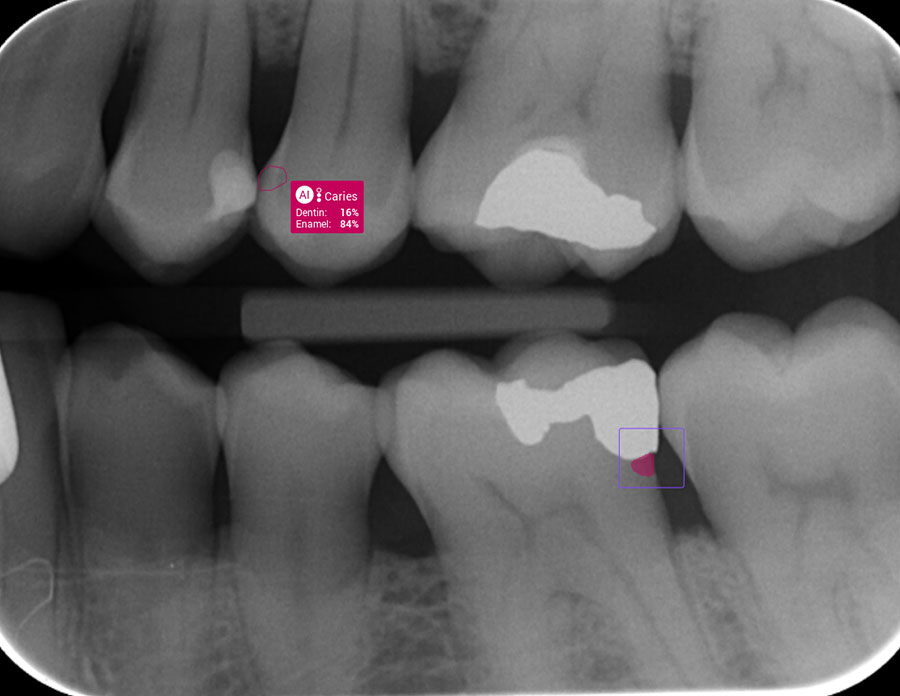

Pearl AI uses artificial intelligence to analyse X-rays in real time, detecting early decay, bone loss, and subtle changes that are easy to miss. Early detection often means no drilling is needed.

Pearl AI identifies decay early, and Curadont Repair stops it before it spreads. Together, they offer a gentle, preventive dental solution.